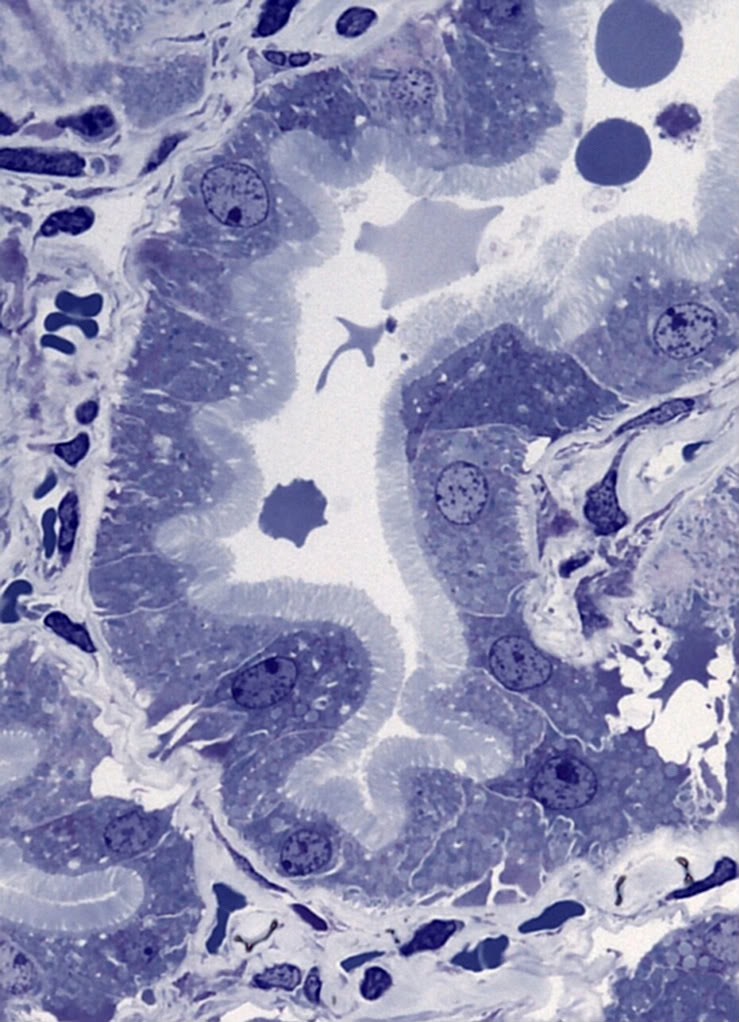

Im Bild Nr 2 in meinem ersten Post erkennt man rechts von der Mitte eine Nierentubuluszelle und daneben das angrenzende Bindegewebe.

Interessanterweise scheint es zwischen beiden einen besonders intensiven Kontakt zu geben, da offenbar Bindegewebsausläufer zapfenförmig in die Zelle hereinreichen !

Ich habe so etwas noch nie gesehen, vielleicht kann jemand helfen ? Jedenfalls ein interessantes Strukturdetail wie ich finde.

Ich habe den Bereich nochmals im angehängten Bild herausvergrössert.

bei der von Dir gezeigten Struktur handelt es sich sehr wahrscheinlich um ein sogenanntes basales Labyrinth. Hierbei handelt es sich um tiefe fingerförmige, manchmal verzweigte  Einstülpungen der Zellmembran in das Zytoplasma der Nierentubuluszelle. Auf diese Weise wird  die zur Resorbtion befähigte Oberfläche der Zelle stark vergrößert.

Die Mikrovilli sieht man sehr schön auf der im Detailbild linken, dem Lumen zugewandten Seite (apikal). Die dortigen Mikrovilli erzeugen in der Tat eine enorme Oberflächenvergrösserung. Ich nehme mal an das es sich hier um den proximalen Tubuls der Nierenschleife handelt http://de.wikipedia.org/wiki/Nephron, auf der vergrösserten Oberfläche sitzen alle möglichen Transportsysteme und molekulare Pumpen.